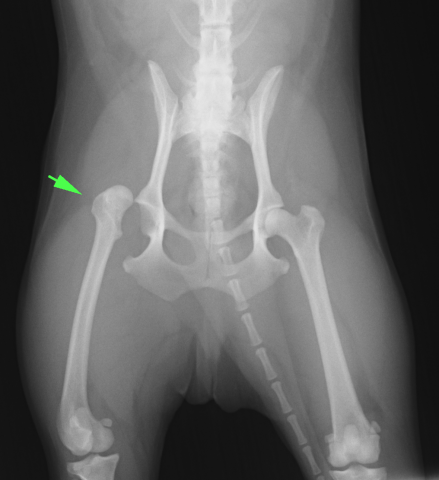

<レントゲン検査>

どちらの方向にずれているか、もともとの股関節の形成不全がないか、骨折がないかなどを調べます。多くは背頭側に外れます。